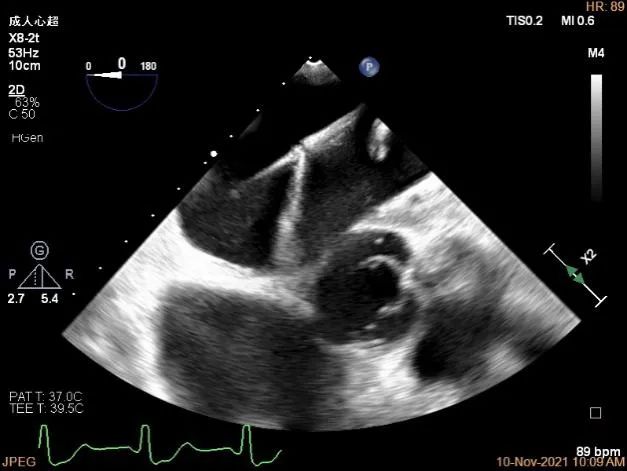

TEE Bicom view:主要病变区域为P1区,瓣叶中部可见连续性中断

确定房间隔穿刺点:略靠前,3D视图2点位